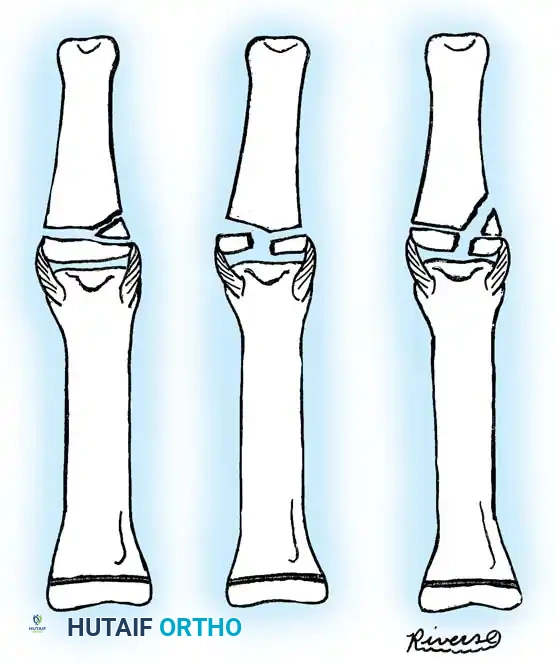

A significant percentage of physeal separations occur at the bases of the middle and proximal phalanges. The vast majority are Salter-Harris type II injuries.

Image

Most type II fractures can be managed successfully with closed reduction and immobilization. The intact periosteal hinge aids in reduction and provides stability. Conversely, Salter-Harris type III and the exceedingly rare type IV fractures require absolute anatomical reduction due to their intraarticular nature.

If closed reduction of a type III or IV fracture is imperfect, ORIF is mandatory. The surgical approach typically involves a mid-axial or dorsal incision, careful elevation of the extensor mechanism, and direct visualization of the articular surface. Fixation is achieved using fine, smooth K-wires (0.028 or 0.035 inch) driven parallel to the joint surface or obliquely across the fracture, minimizing physeal trauma.